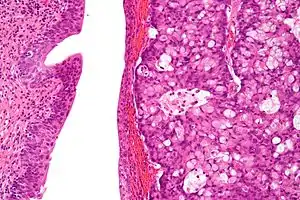

| Micrograph of urachal carcinoma (right of image) and non-malignant urothelium (left of image). H&E stain. | |